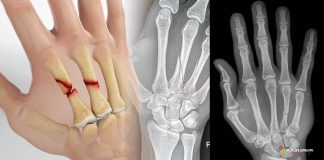

Boksör Kırığı (Beşinci Metakarp Kırığı)

Boksör kırığı, klasik olarak yumruk atma mekanizmasıyla oluşan 5. metakarpal boyun kırığıdır ve tüm el kırıklarının yaklaşık %10’unu oluşturur. Özellikle 5. metakarpal kırıkları, yani...

Metakarp Kırıkları Acil Yaklaşım

Metakarp kırıkları, üst ekstremitenin en sık karşılaşılan kemik yaralanmaları arasında yer alır. Genel popülasyonda yaygın olarak görülmekle birlikte, temas sporlarıyla uğraşan sporcularda (örneğin boksörler...